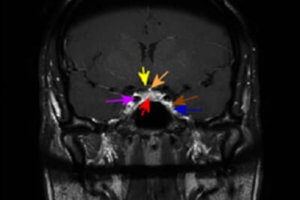

Cavernous Sinus Anatomy

Situated in the midline just above the skull base and bridging the sphenoid and temporal bones, the cavernous sinus is a collection of venous channels that serves as a major conduit for... Read more »